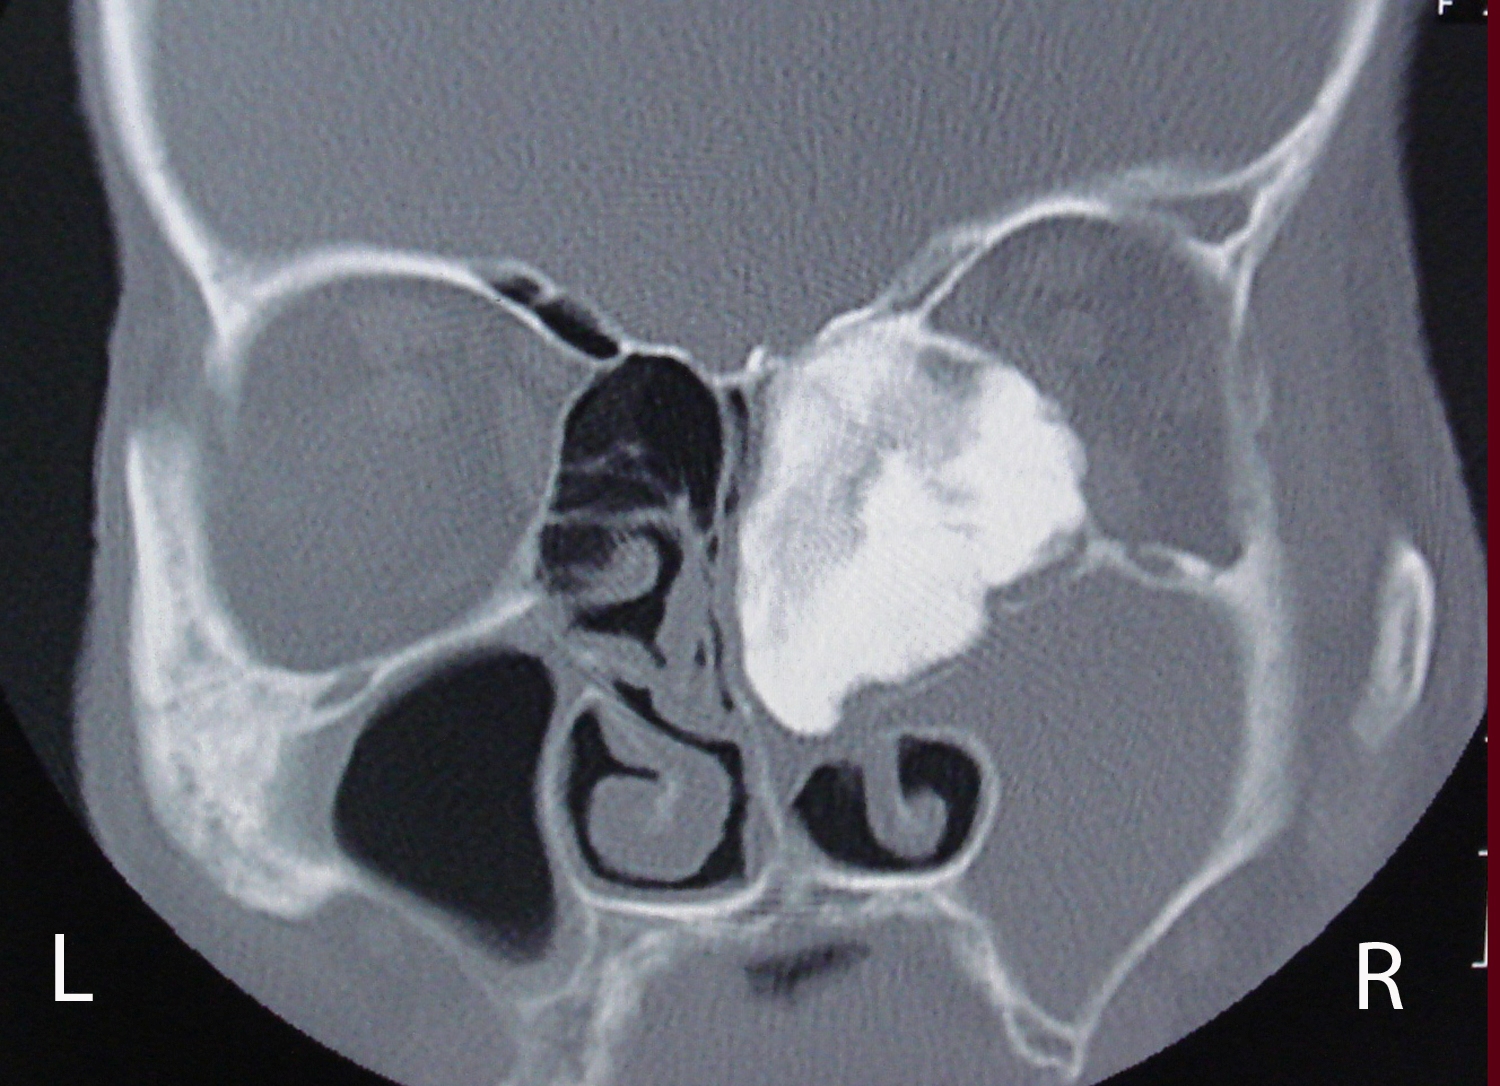

Osteoma is the most frequent benign tumor of paranasal sinuses. Usually osteomas are asymptomatic and discovered incidentally during radiological imaging for other reasons. A giant osteoma with intraorbital extension is rare. Plain radiograph may be useful; however CT scan is the best modality of investigation for diagnosing and treatment planning. In asymptomatic osteomas, serial follow-up can be done. Surgery is performed in the presence of symptoms and signs. We report a case of 60 years old woman with a large osteoma of right ethmoid sinus extending into the ipsilateral orbital cavity.